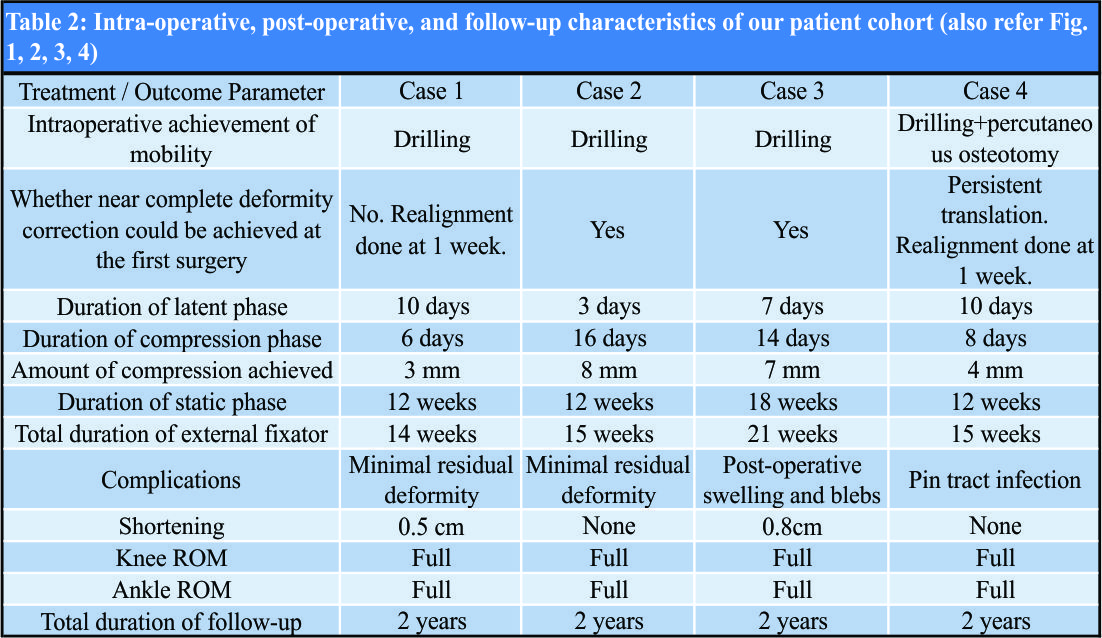

We had four children (3 males and 1 female, age 4–15 years) with hypertrophic nonunion of the tibia. Three of them were post-traumatic. The fourth patient had tibial bone defect following acute osteomyelitis. He underwent tibialisation of the fibula elsewhere. The distal junction united uneventfully, but the proximal junction went in for hypertrophic nonunion. The demographic and clinical characteristics of our patient cohort are summarized in Table 1 (Fig. 1, 2, 3, 4).

All patients were operated in the supine position in radiolucent table under radiological monitoring. The fibula was osteotomized through a stab incision at the junction its middle and lower third in three of the cases (one patient lacked fibula due to prior tibialisation). Mobility of the pseudarthrosis was reassessed at this stage, and all nonunions were stiff. Ilizarov apparatus was assembled in the standard fashion with its proximal and distal modules parallel to their respective segments. Once the rings were assembled independently in proximal and distal segments, the fracture site was accessed through a stab incision. Vigorous drilling of the pseudarthrosis was done with 4.5mm drill bit, and the pseudarthrosis was made relatively mobile (one case needed passage of osteotome percutaneously to achieve mobility). At this stage, deformity correction was attempted by making the proximal and distal modules parallel to each other and connecting them with straight rods. Near-complete deformity correction was achieved on the table in two of our cases. In the other two, there was residual deformity. A complete correction was not attempted as there would be undue stretch of the soft tissue otherwise. Both these cases were taken for realignment under anesthesia after a week, and complete deformity correction was achieved.

Post-operative care

Compression at the pseudarthrosis was used as the sole post-operative strategy. It was ensured during surgery (as much as possible) that there was no residual translational or rotational deformity. After a latent period of 3 days, minor residual deformity correction in the coronal or sagittal plane was performed by differential compression of the connecting rods.  Once this was achieved, compression was applied all around the pseudarthrosis at a rate of 0.5 mm per day until there was good approximation of cortices radiologically in orthogonal views. The patients were made to mobilize the knee and ankle (the ankle was spanned in one patient where the pseudarthrosis was in the distal fourth of the tibia) and bear weight fully with support. The patients were taught pin tract care and asked to go home with proper instructions for rehabilitation and were asked to follow-up once in 6 weeks or whenever necessary.

Once this was achieved, compression was applied all around the pseudarthrosis at a rate of 0.5 mm per day until there was good approximation of cortices radiologically in orthogonal views. The patients were made to mobilize the knee and ankle (the ankle was spanned in one patient where the pseudarthrosis was in the distal fourth of the tibia) and bear weight fully with support. The patients were taught pin tract care and asked to go home with proper instructions for rehabilitation and were asked to follow-up once in 6 weeks or whenever necessary.

All patients had a follow-up of 2 years from the removal of external fixator. All four non-unions united uneventfully. In the two patients were deformity correction was completed in two stages, compression commenced after 3 days after second surgery. (No manipulation was done during the week in between two stages as it would inadvertently stretch the soft tissue.) Another patient (where all deformities were acutely corrected) developed minimal swelling of the limb and blebs on the 2nd day. It responded to limb elevation and delay of rehabilitation. Compression was started after a latent period of 7 days. In the fourth patient, the latent phase lasted only for 3 days. After completion of “dynamic” phase, patients were sent home with advice to follow-up every 6 weeks. Three of the nonunions were united at the second follow-up (12 weeks) and the fourth at third follow-up (18 weeks). Thus, the total duration of external fixator was 14 weeks in one patient, 15 weeks in two patients, and 21 weeks in the fourth patient. The fixators were removed after satisfactory stress test after loosening all connecting rods. Patellar tendon bearing cast was given for all cases for 6 weeks with the advice of full weight-bearing. Apart from limb swelling and blebs in one case, another patient had pin tract infection that was detected at first follow-up that needed a week of dressings and oral antibiotics. The infection settled uneventfully without any need of wire exchange. Two patients each had minimal residual deformity and shortening <1 cm, well within acceptable limits with potential to remodel. The intraoperative, post-operative, and follow-up characteristics of our patient cohort are summarized in Table 2 (Fig. 1, 2, 3, 4).

The fixators were removed after satisfactory stress test after loosening all connecting rods. Patellar tendon bearing cast was given for all cases for 6 weeks with the advice of full weight-bearing. Apart from limb swelling and blebs in one case, another patient had pin tract infection that was detected at first follow-up that needed a week of dressings and oral antibiotics. The infection settled uneventfully without any need of wire exchange. Two patients each had minimal residual deformity and shortening <1 cm, well within acceptable limits with potential to remodel. The intraoperative, post-operative, and follow-up characteristics of our patient cohort are summarized in Table 2 (Fig. 1, 2, 3, 4).